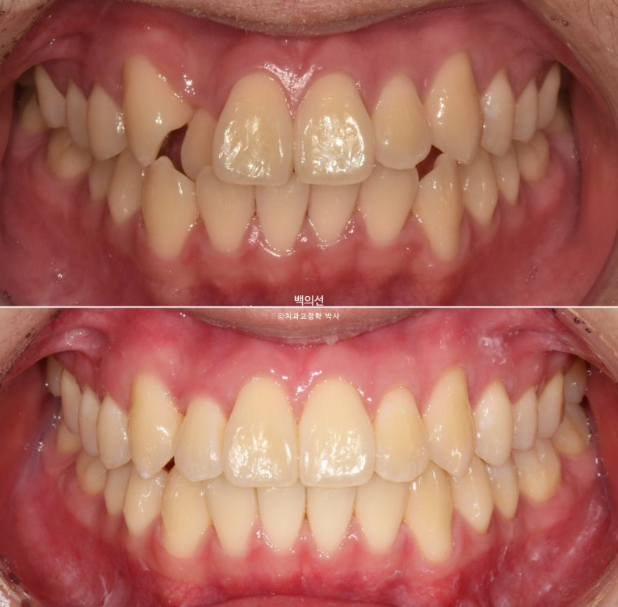

전 후 비교 보겠습니다.

24.04~25.07

덧니와 반대교합은 해소가 되었습니다.

교합은 좋고 양쪽 다 1급 교합관계를 보입니다.

배열도 완벽 합니다.